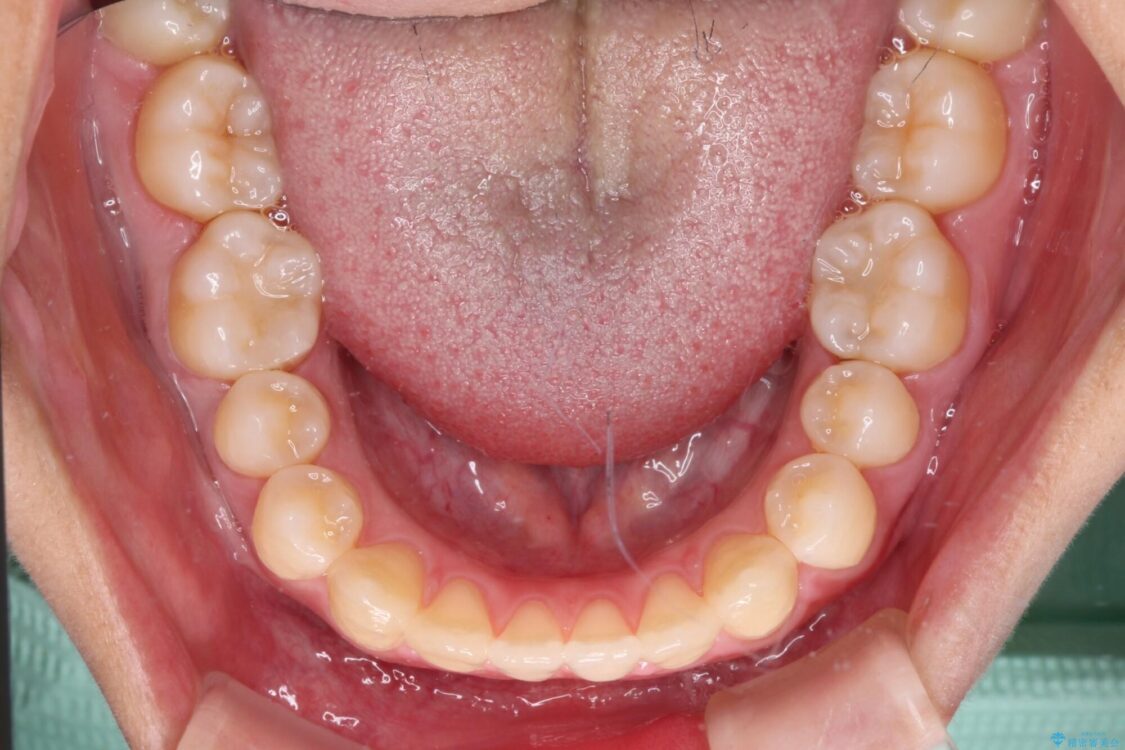

治療前

• 隙間だらけの歯列 インビザラインで改善 治療前画像